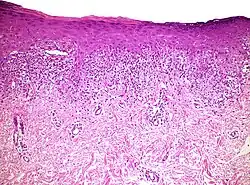

| Mycosis fungoides | Present | Focal | Regular or irregular | Normal | Normal | Minimal or no spongiosis; ±Pautrier microabscess | Atypical lymphoid cells lining the dermo–epidermal junction | ![]() |